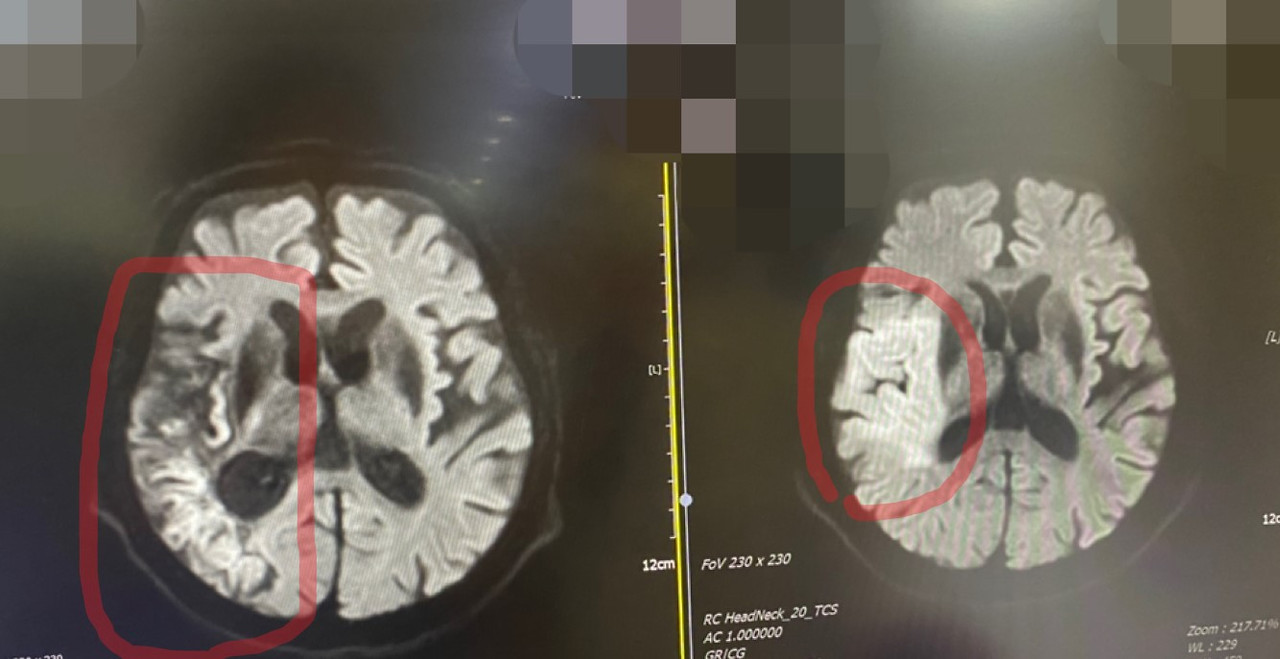

<엄마의 MRI사진. 골든타임을 놓쳐 결국 굳어버린 뇌>

뇌경색이라서 혈전용해제를 투여해야 한다고 했다.

"결국, 골든타임을 놓쳤다"

“위기는 넘겼습니다. 뇌경색이 상당부분 많이 진행됐지만. 연세가 있으셔서 수술은 하지 않고 약물로 치료할 예정입니다. ”